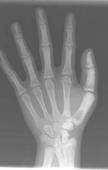

骨硬化病即石骨癥(osteopetrosis),又稱大理石骨病,其特點是全身性骨質(zhì)硬化,骨塑型異常,進行性貧血,肝脾腫大,容易骨折,往往有家族史。

- 常見癥狀:面色蒼白、 眼距寬闊、 兒童反復骨折前囟飽滿、 脊柱側(cè)彎 、髖內(nèi)翻耳聾、 腦積水 、貧血、 視神經(jīng)萎縮 、方顱、前囟飽滿、眼距寬、失明、骨折、